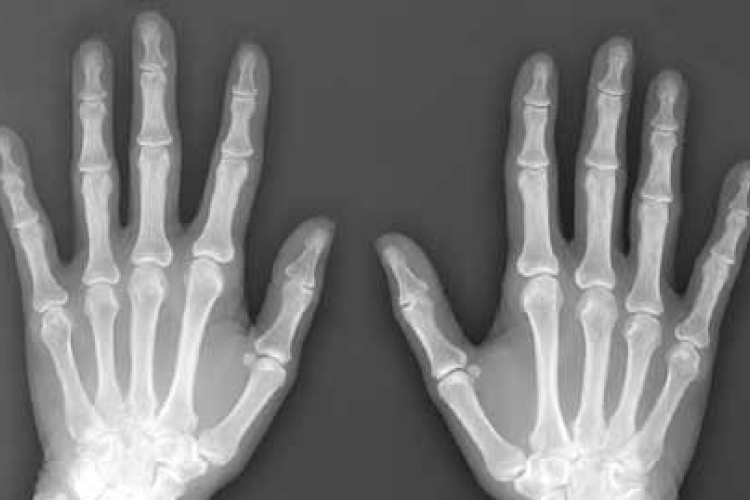

A magzatvíz visszafordíthatja a csontok öregedését

A magzatvízben lévő őssejtek újjáéleszthetik az öregedő és gyenge csontokat - állítják brit kutatók, akik szerint felfedezésük segíthet genetikai betegséggel született gyerekeken, idős embereken és űrhajósokon is.